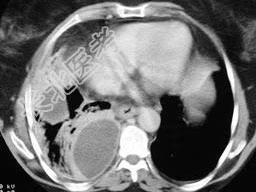

- 单项选择题男,54岁, 发热、胸痛一月余,继往有酗酒史, 请结合CT图像选择最可能的诊断 ( )

A、脓胸

B、肺脓肿

C、大叶性肺炎

D、肺囊虫病

E、肺癌